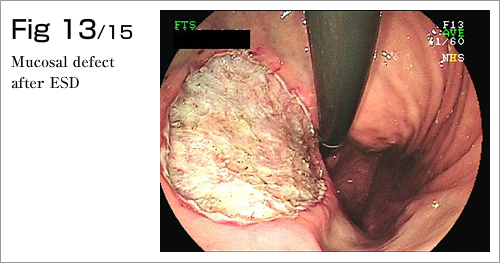

The procedure is done in several steps. First, the margins of the lesion are marked by electrocautery, and then a submucosal injection is used to lift the lesion (Diagram 4-8). After which, a circumferential incision into the submucosa is made around the lesion (Diagram 9). Finally, the lesion is dissected from underlying deep layers of GI tract wall with electrocautery knife and removed (Diagram 10-13). The lesion, mainly existing in the mucosal layer (1st layer), can be completely excised along with the submucosa (2nd layer)(Diagram 14-15).

Dr. Mitooka has developed a novel and simple technique for the complete closure of large mucosal defects after ESD with hemoclips and fishing line using a conventional one-channel endoscope (up to 3cm in diameter for gastric specimens & 5cm in diameter for colonic specimens) allowing safer ESDs. ESD is a minimally invasive operation best suited for earliest stage of cancers and premalignant lesions, so that ESD in one day is possible. For those of you in need of ESD treatments and are busy, limited for time, or wish for a new treatment in one working day, please contact us.